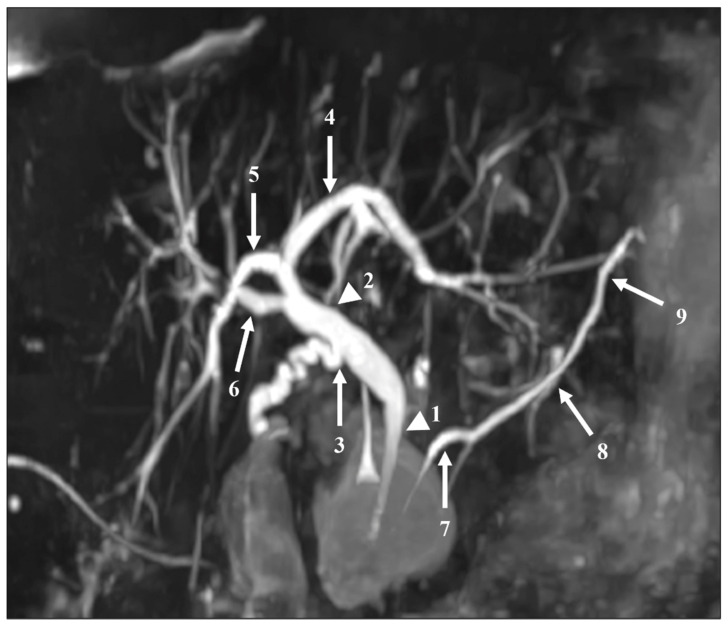

The readers also assessed the visualization of 12 segments of the pancreatic and bile ducts: the proximal and distal parts of the CBD; the confluence of the cystic duct and CBD; the proximal, central, and distal parts of the MPD; the intrahepatic bile ducts (IHBDs) to their primary branches (right and left IHBDs) and secondary branches (right anterior and posterior sectoral ducts and left medial and lateral branches). Each of these 12 segments were evaluated using a five-point Likert scale, with higher scores indicating better duct visualization (Table 2). Figure 2 shows these segments on an MIP reconstruction of a CS-BH-MRCP image.